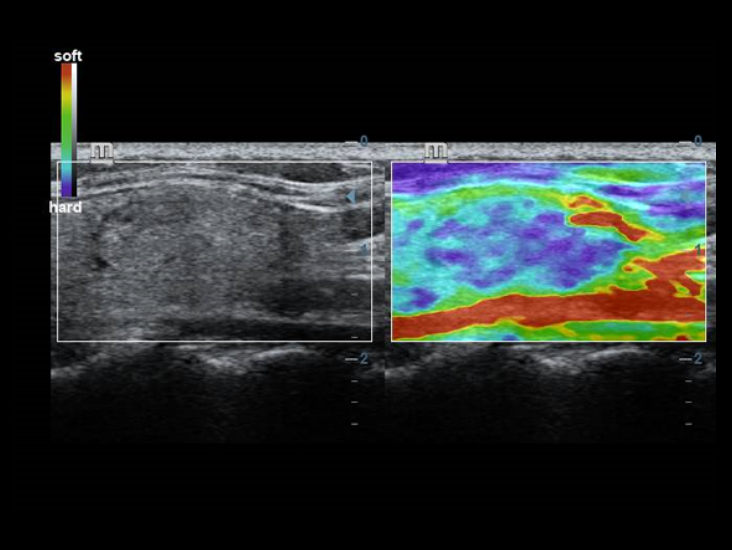

Klassieke beeldvormingstechnologie?n: verbetering van de kwaliteit voor diagnoses

DC-40 met Full HD maakt gebruik van klassieke beeldvormingstechnologie?n die van gevestigde ultrasoundsystemen zijn gemigreerd om u beelddetails van betere kwaliteit te bieden.

- iClear (beeldvormingstechnologie die spikkels reduceert)

- PSH (Phase Shift Harmonic-beeldvorming)

- iBeam: ruimtelijke beeldvormingstechnologie